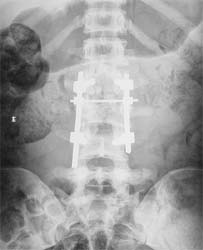

患者男性,30岁,腰3骨折,截瘫

CT显示腰3椎体爆裂,骨块凸入椎管压迫硬膜囊

施行后路椎管前方减压术及经椎弓根固定植骨术,彻底解除 脊髓前方的压迫及后凸畸形,截瘫部分恢复